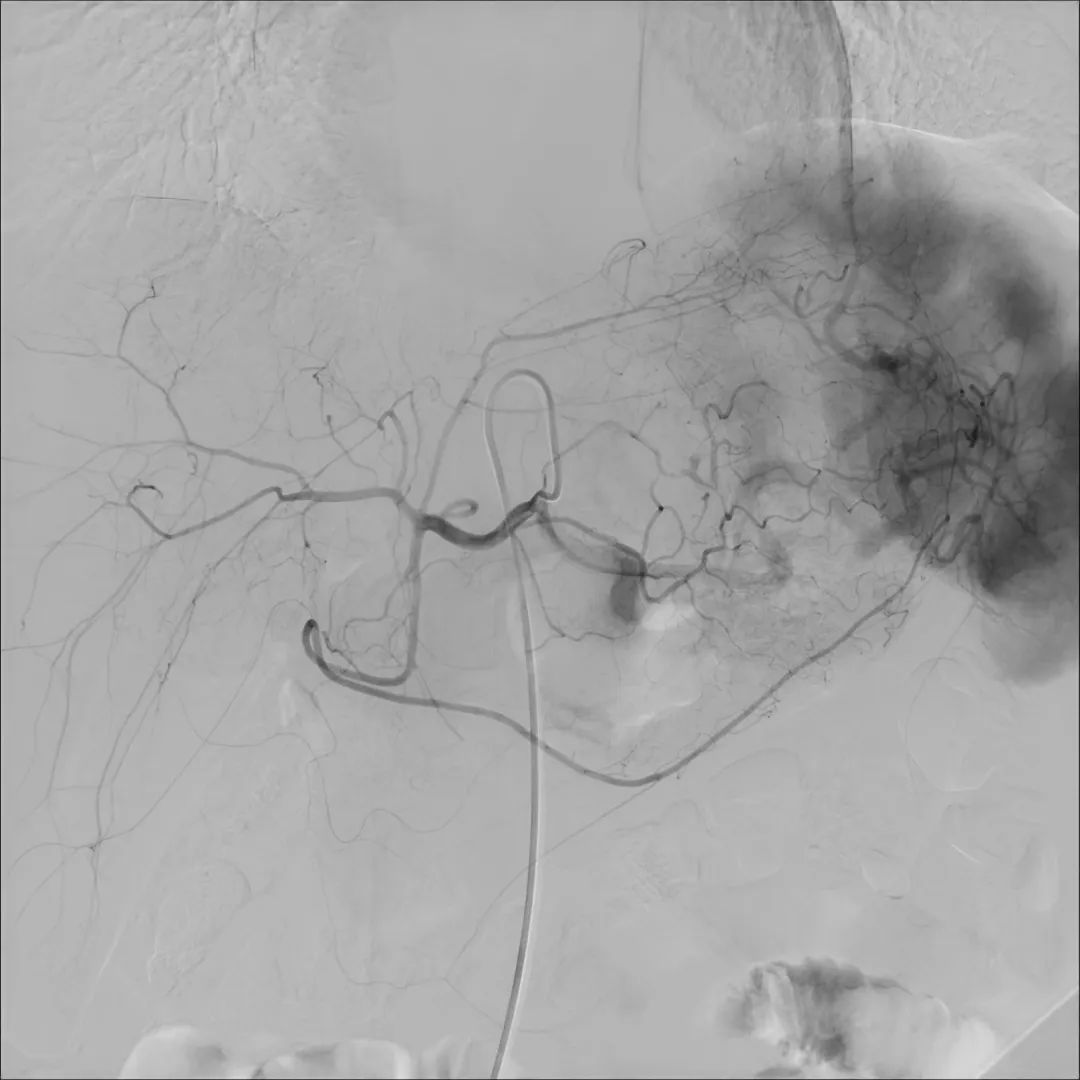

目前,唯邁醫(yī)療的DSA已裝機(jī)眾多三甲醫(yī)院,而剛剛完成裝機(jī)的濟(jì)南三院也在數(shù)日內(nèi)完成幾十例介入手術(shù),涵蓋經(jīng)介入造影治療,外周血管造影治療,心臟造影支架置入,滿足臨床多科室使用。

肝動(dòng)脈造影治療

支氣管動(dòng)脈造影治療